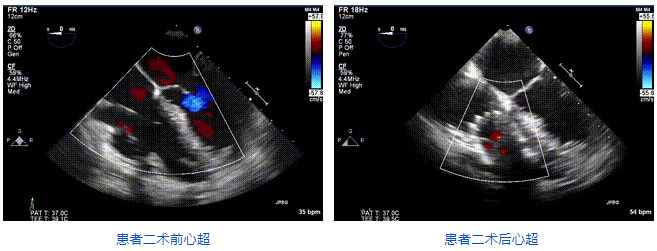

2021年12月24日,復(fù)旦大學(xué)附屬中山醫(yī)院葛均波院士團(tuán)隊成功應(yīng)用LuX-Valve Plus為一例極重度三尖瓣反流(TR)合并房顫、房缺的患者完成了經(jīng)血管三尖瓣置換術(shù),這是在前基礎(chǔ)上,本周完成的第三例經(jīng)血管三尖瓣置換手術(shù),葛均波院士、周達(dá)新教授等與心外科魏來教授、賴顥教授,心超室的潘翠珍教授、李偉教授及麻醉科的郭克芳教授共同完成了本周手術(shù),均獲得圓滿成功!患者術(shù)后超聲顯示無TR,臨床癥狀明顯改善。本周手術(shù)的成功也為LuX-Valve Plus救治性臨床研究添上了濃墨重彩的一筆。

三例患者入院后,葛均波院士團(tuán)隊周達(dá)新教授、潘文志教授、張源博士、陳莎莎博士及心超室的潘翠珍教授、李偉教授對患者的情況進(jìn)行詳細(xì)評估和討論,最終決定為三例患者選擇LuX-Valve Plus40mm、50mm和50mm型號的瓣膜進(jìn)行手術(shù)治療。手術(shù)后即刻拔除氣管插管,術(shù)后患者三尖瓣反流癥狀得到顯著改善,復(fù)查心超結(jié)果顯示人工三尖瓣瓣膜支架固定穩(wěn)定,瓣葉關(guān)閉形態(tài)未見異常,未見明顯反流。

LuX-Valve Plus是LuX-Valve系列產(chǎn)品的第二代,采用的是經(jīng)血管入路的全新輸送系統(tǒng),其設(shè)計開發(fā)過程得到了上海中山醫(yī)院葛均波院士及其團(tuán)隊的精心指導(dǎo),研究結(jié)果提示瓣膜植入的安全性和有效性俱佳,尤其瓣膜獨特的設(shè)計使其具有極佳自適應(yīng)性,本周三例患者病因及解剖結(jié)構(gòu)各具特點,但均可從LuX-Valve Plus植入術(shù)明顯獲益。目前,LuX-Valve Plus已在全國各中心開展救治性臨床研究,相信未來定會為更多的三尖瓣反流患者帶來福音。